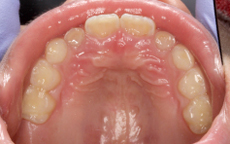

【症例2】

矯正をスタートして半年目です。それぞれの歯がしっかりした位置に並んできました。